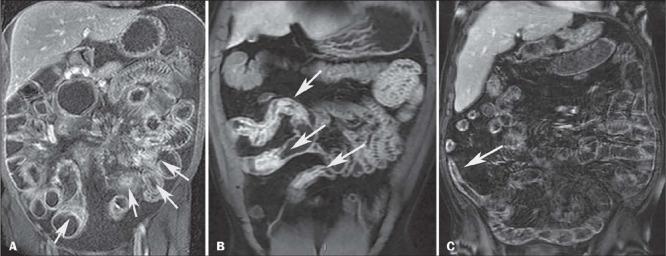

Crohn's disease is an inflammatory bowel disease that can affect any segment of the gastrointestinal tract. It has a variable clinical course, with alternating periods of disease activity and remission. Because the incidence and prevalence of Crohn's disease have been increasing, evaluation by imaging methods has become more important. The most widely used methods are computed tomography enterography, magnetic resonance enterography (as an elective examination), and contrast-enhanced computed tomography (in the context of emergency). Computed tomography enterography and magnetic resonance enterography are useful for diagnosis, follow-up, evaluation of complications, and prognosis. Both can be used in order to evaluate the small bowel loops and the associated mesenteric findings, as well as to evaluate other abdominal organs. They both also can detect signs of disease activity, fibrosis, penetrating disease, and complications. The interpretation of such changes is essential to the multidisciplinary approach, as is the standardization of the nomenclature employed in the reports. In this paper, we review and illustrate the imaging findings of Crohn's disease, using the standardized nomenclature proposed in the multidisciplinary consensus statement issued by the Society of Abdominal Radiology, the Society of Pediatric Radiology, and the American Gastroenterology Association, with recommendations for descriptions, interpretations, and impressions related to those findings.

克罗恩病是一种炎症性肠病,可累及胃肠道的任何节段。其临床病程多变,疾病活动期和缓解期交替出现。由于克罗恩病的发病率和患病率一直在上升,通过影像学方法进行评估变得更加重要。最常用的方法是计算机断层扫描小肠造影、磁共振小肠造影(作为选择性检查)和增强计算机断层扫描(在急诊情况下)。计算机断层扫描小肠造影和磁共振小肠造影对诊断、随访、并发症评估及预后判断均有帮助。两者均可用于评估小肠肠袢及相关肠系膜表现,以及评估其他腹部器官。它们还都能检测疾病活动、纤维化、穿透性病变及并发症的征象。对这些改变的解读对于多学科诊疗方法至关重要,报告中使用的命名标准化也同样重要。在本文中,我们使用腹部放射学会、儿科放射学会和美国胃肠病学会发布的多学科共识声明中提出的标准化命名,回顾并阐述克罗恩病的影像学表现,并对与这些表现相关的描述、解读及印象给出建议。